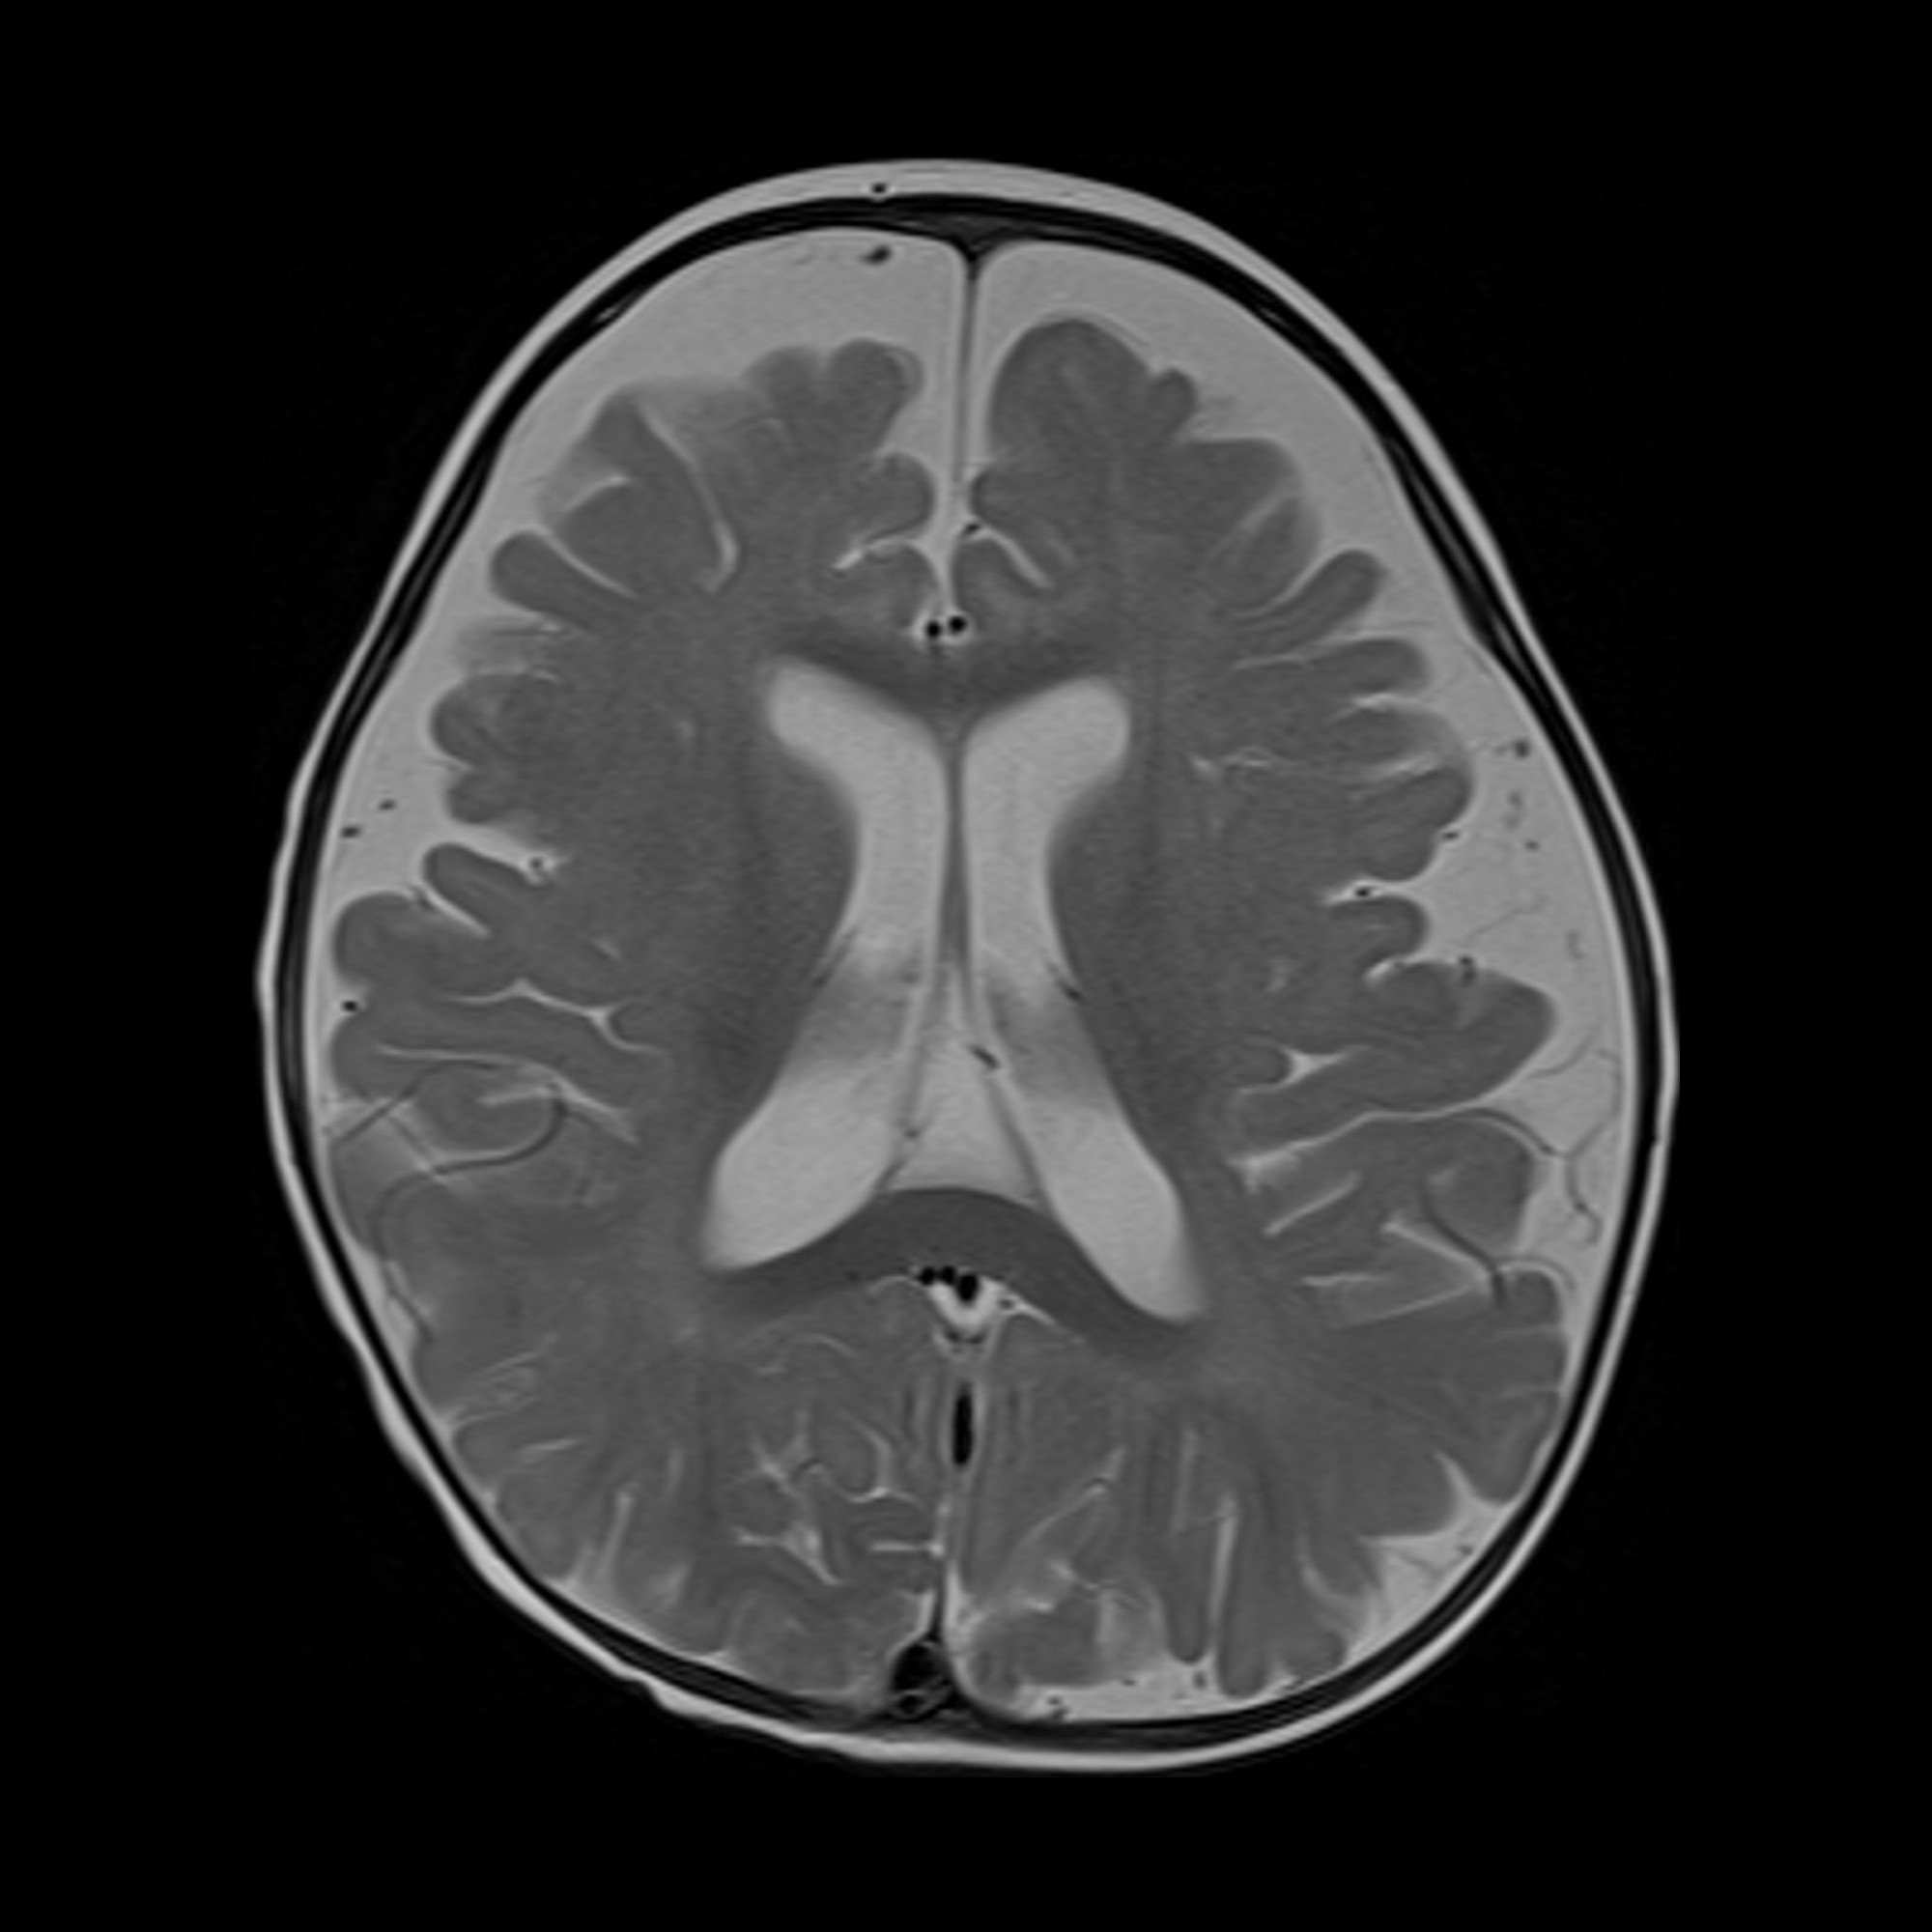

Doctors and family members are closely monitoring a newborn boy named Noah, who remains under intensive medical care as he faces a serious brain tumor diagnosed shortly after birth. Born significantly underweight and physically fragile, Noah is spending his earliest days surrounded by medical equipment, guided by constant care and quiet determination.

Medical specialists have explained that treating a brain tumor in a newborn presents exceptional challenges due to the baby’s size and developing body. While the road ahead remains uncertain, the care team is focused on keeping Noah stable and as comfortable as possible while evaluating next steps.